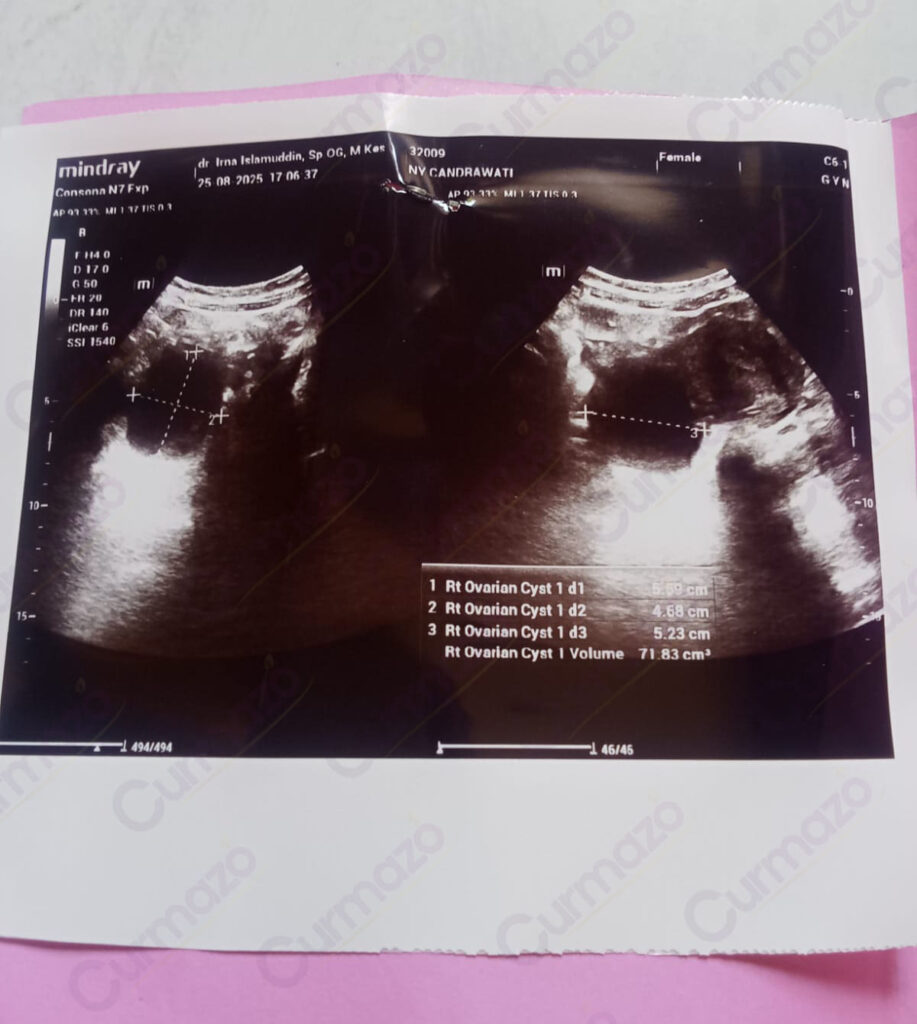

25 Agustus 2025, setelah pulang kerja badan saya rasanya capek sekali dan perut bagian bawah terasa nyeri, akhirnya saya pergi cek ke dokter kandungan. Saya kaget sama hasil USG nya. Ternyata saya ada 3 kista yang berukuran 5.59 cm, 4.68 cm, dan 5.23 cm. Disitu saya baru paham, ternyata gejala yang selama ini saya alami itu disebabkan oleh kista.

Foto hasil USG before: